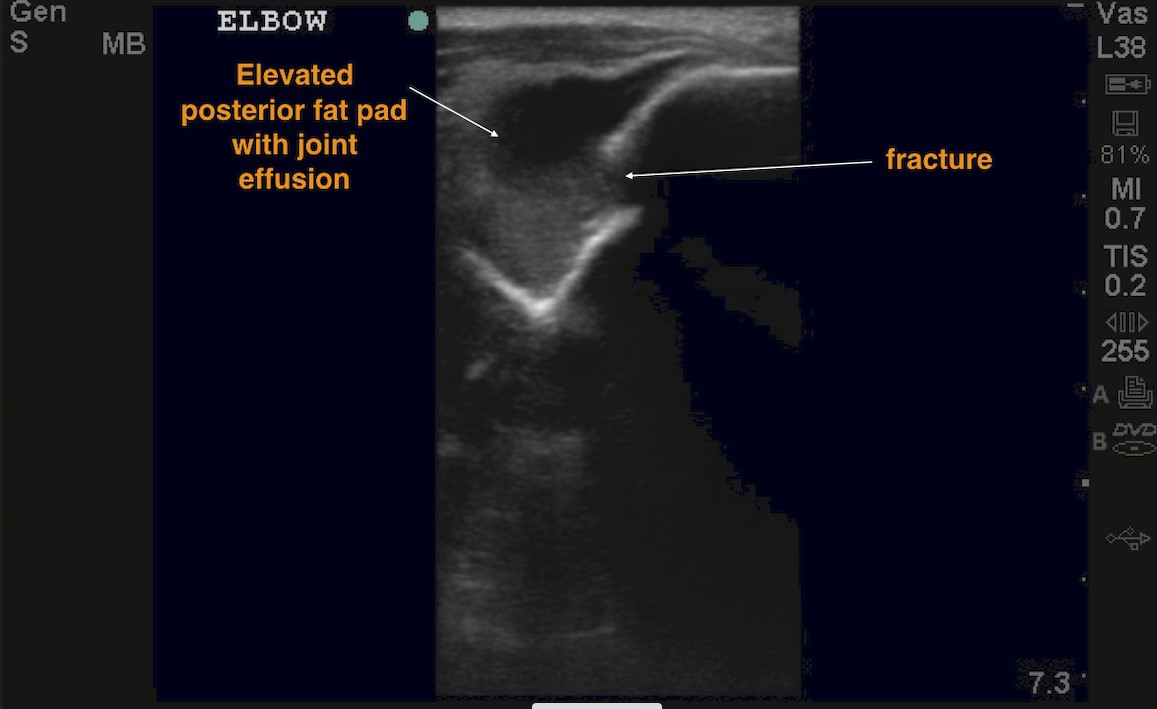

Bulging posterior fat pad: rise of the fat pad (Sail sign) above the extension of the distal humeral line on longitudinal view (Figure 4) or above a line connecting both lips of the olecranon fossa on transverse view (Figure 5).

Figure 5: Transverse axis of the elbow depicting the olecranon fossa and a large joint effusion with a disruption of the cortex.